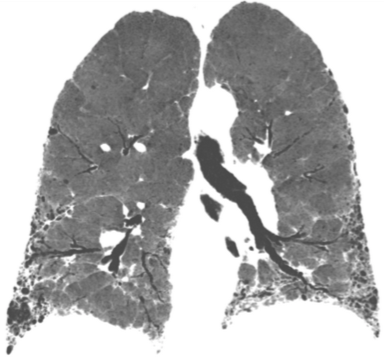

La fibrosis pulmonar idiopática es la enfermedad pulmonar intersticial mas frecuente y no se conoce la causa que la provoca. Origina un endurecimiento o cicatrización progresiva (fibrosis) del tejido pulmonar que hace que el paciente presente fatiga con los esfuerzos y a veces tos irritativa con lo que el paciente pierde de forma acelerada capacidad […]